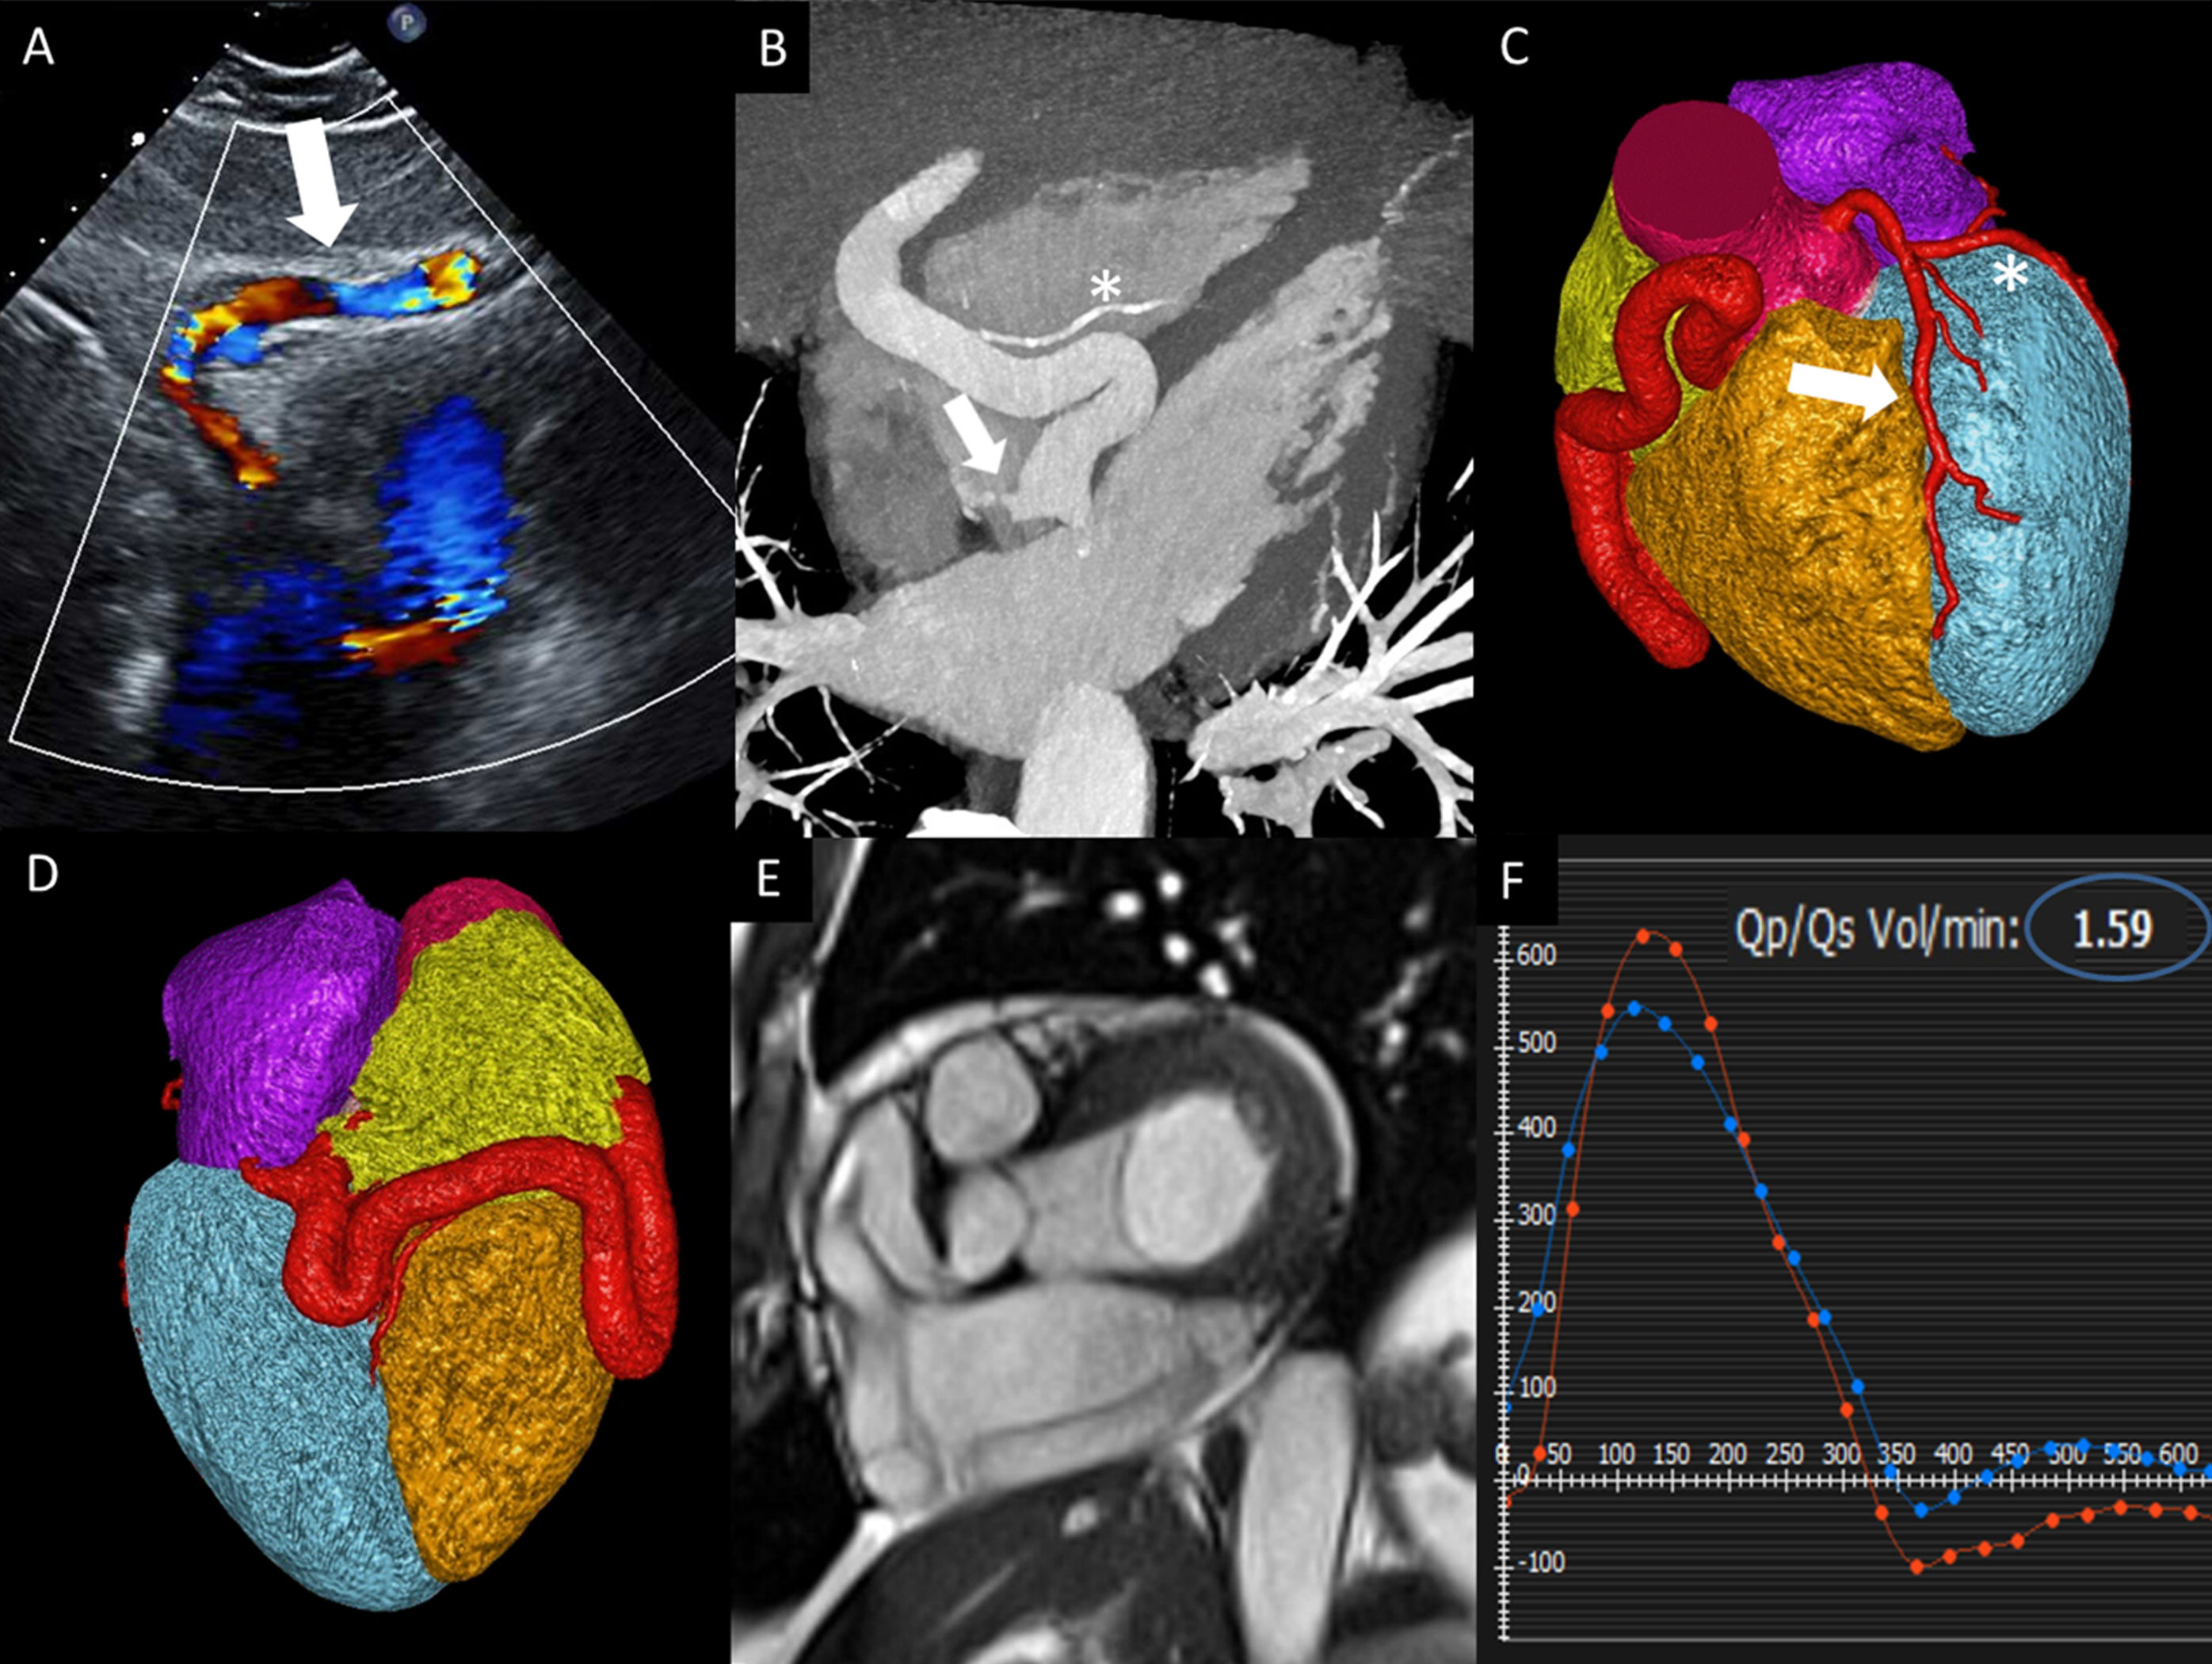

An asymptomatic 64-year-old man presented for cardiovascular evaluation due to a systolic murmur. Transthoracic echocardiogram with Doppler demonstrated flow in a tubular structure between the liver and the right ventricle in the subcostal view (arrow figure 1A), as well as abnormal flow into the coronary sinus (video 1 of the supplementary data). Cardiac computed tomography was performed for further evaluation. The multiplanar reconstruction, at a similar angle to the echocardiogram, showed a diffusely aneurysmal and tortuous right coronary artery (RCA) measuring up to 1.4cm in diameter with a fistulous connection to the coronary sinus at the entrance of the right atrium (arrow figure 1B). The posterior descending artery was normal in size without evidence of aneurysm (asterisk figure 1B). Volume rendering reconstructions (figure 1C,D) compare the aneurysmal and tortuous RCA to the normal left anterior descending artery (arrow figure 1C) and left circumflex artery (asterisk figure 1C). Cardiac magnetic resonance (CMR) was performed to evaluate the functional impact of the fistulous connection (video 2 of the supplementary data). Figure 1E and video 2 of the supplementary data show short-axis cine images with the aneurysmal proximal, mid, and distal segments of the RCA. Phase-contrast CMR demonstrated a pulmonary to systemic flow ratio (Qp/Qs) of 1.6 (blue circle figure 1F), consistent with a significant left-to-right shunt. At this time, the patient has received no treatment and is waiting for follow-up imaging.

We present a very rare case of a fistula between an aneurysmal RCA and the coronary sinus with a multimodality evaluation integrating complex anatomy and function.